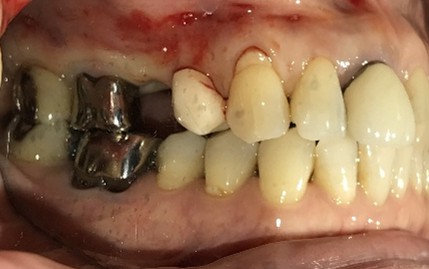

男性Kさん 50代(インプラント)

主訴

歯がグラグラするところ、むし歯のところ、しみるところ、被せ物がとれたところ、歯茎が腫れて血が出るところ、歯が抜けているところがある。すべて治したい。

治療内容

残っている歯を抜歯し、上下インプラント治療をしました。

所感

歯周病が進行している歯、むし歯が進行している歯がほとんどで、レントゲンを撮り、詳しく診てみると、ほとんどの歯を保存することができないことがわかりました。抜歯後は、入れ歯かインプラントの方法があります。治療開始前に患者さんに詳しく現状を説明し、治療法についてじっくり相談しました。自分の歯と同じような感覚で食事できるインプラント治療を選択されました。治療後、表情がとても明るくなり、口元がとても自然で10歳以上若返ったように感じました。「時間はかかりましたが、インプラントにして本当に良かったです!」と素晴らしい笑顔でお話ししてくださいました。